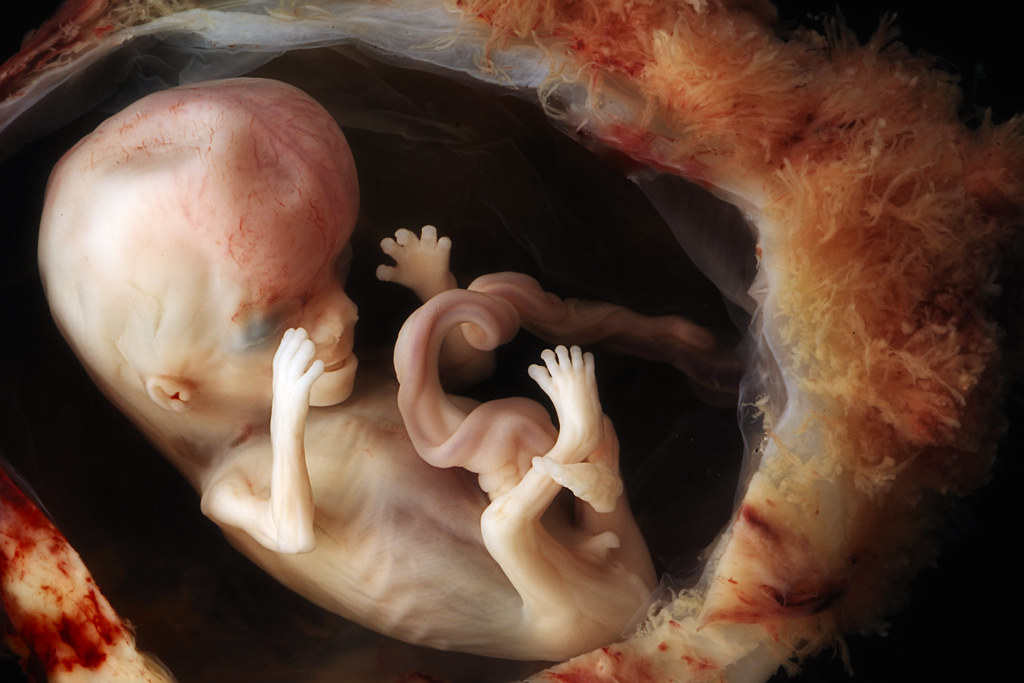

Report: Number of babies killed annually during IVF is now more than those lost to abortion November 12, 2025